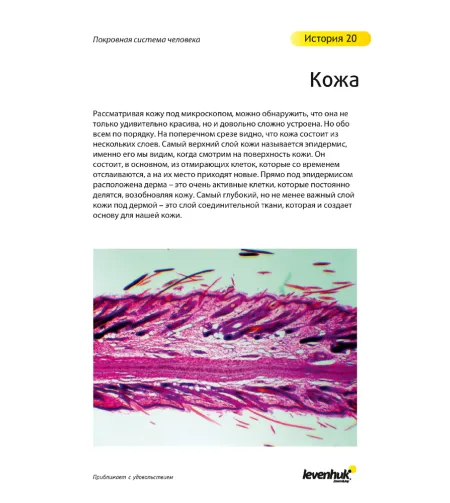

"See it all! Exploring the World Around Us" User Guide Sample Pages